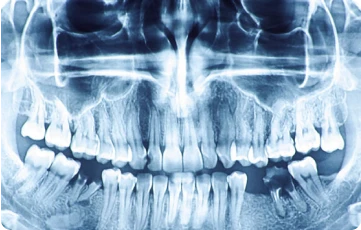

Sử dụng công nghệ tiên tiến như X-quang kỹ thuật số và máy cắt laser, mang lại chẩn đoán chính xác và điều trị hiệu quả.

Tại Nha khoa Venus, dịch vụ cạo vôi răng được thực hiện bởi đội ngũ bác sĩ giàu kinh nghiệm, sử dụng thiết bị hiện đại và công nghệ tiên tiến. Quy trình bao gồm các bước: thăm khám và tư vấn, chụp X-Quang và lên phác đồ, tiến hành cạo vôi răng, đánh bóng răng và hoàn thành điều trị. Đặc biệt, khách hàng sẽ luôn cảm thấy thoải mái nhờ kỹ thuật nhẹ nhàng, an toàn và không gây đau nhức.